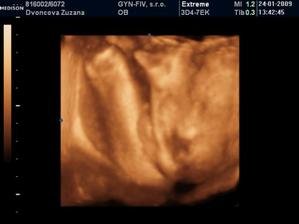

24.1.2009 nám pán doktor prezradil na 3D, že čakáme chlapčeka :o) ....po dlhom rozhodovani sme si povedali, ze to bude maly Nicolas...uz sa velmi tesime, ked pride na svet...caka ho tu cela velka rodina, ktora ho uz teraz velmi lubi :o))